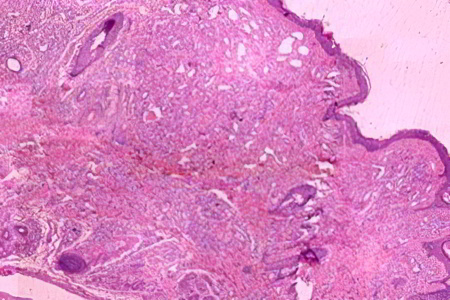

Красные родинки бывают двух типов: капиллярные и кавернозные.

Капиллярные гемангиомы представляют собой скопления сосудов, плотно прилегающих друг к другу. Каждый сосуд состоит из стенки, образованной мембраной и одним или несколькими слоями клеток, похожими на эпителиальные. Просветы этих мелких сосудов заполнены кровяными клетками. В некоторых случаях сросшиеся капилляры формируют дольки, разделенные тонкими перегородками.

Кавернозные родинки состоят из полостей различной формы и размера. Эти полости выстланы клетками эндотелия, напоминающими эндотелий капилляров. Иногда происходит разрыв перегородок между полостями, что приводит к образованию сосочков в образовавшемся пространстве.